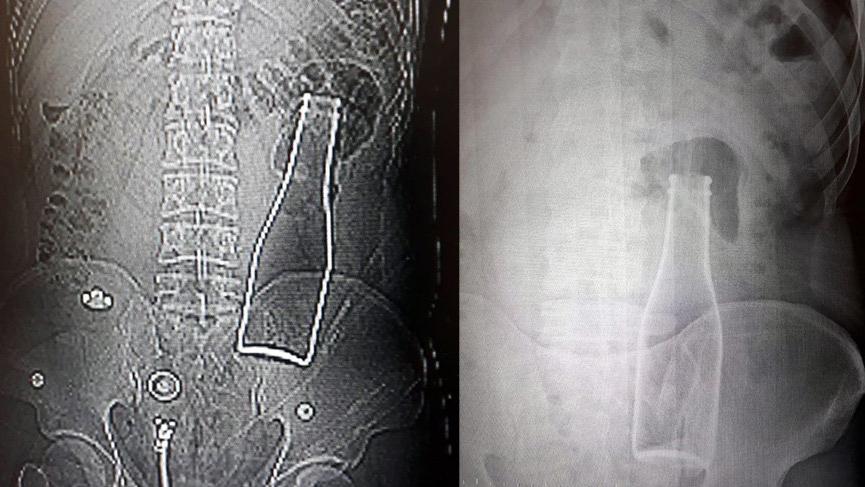

Bunun üzerine röntgen filmi çekilen gencin kalın bağırsağında şişe olduğu görüldü. Makattan girdiği belirlenen şişe, yaklaşık bir saat süren ameliyatla çıkarıldı.